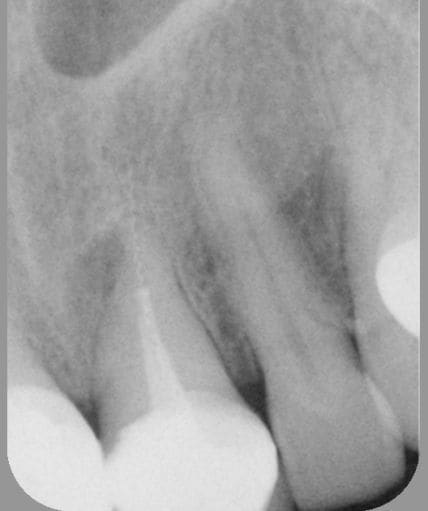

21 preop toajac - Eugenol

21 preop jzjhne - Eugenol

21 preop ipjgeu - Eugenol

21 preop elzmci - Eugenol

21 postop pomtkz - Eugenol

YEEEESSSSS!!! ça marche!

joli travail.

Alors t'as fait quoi pr retirer ce lentulo?:

tentative de ttt orthograde? Microendochir d'emblée? ou peut être les 2?

La rvg postop est J+combien....

La radio post op a été effectué environ 50 minutes après la préop.

Pas de chir apicale, juste un retrait par voie orthograde dans ce cas, après avoir bien vibrer le lentulo et être passé à coté avec une lime K15, je l'ai retiré en le saisissant le plus bas possible avec une pince de Steiglitz.

L'obturation est au Thermafil.

Bien sûr qu'il y a un peu de fierté, mais dans ce cas précis, je ne pense que cela était indispensable, car la lésion était plutôt latéroradiculaire et sans rapport avec l'instrument en question. Mais avant de se dire "je le laisse en place", il faut quand même essayer de le retirer (en tenant compte du rapport bénéfice/risque bien sûr). Et puis, c'est assez jouissif de retirer un fragment de 10 mm de long dépassant de 4 bons mm dans le périapex !